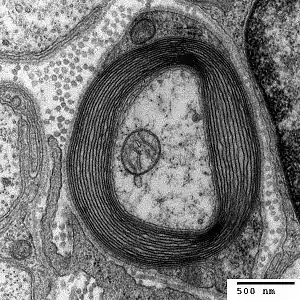

There are two types of axons in the nervous system: myelinated and unmyelinated axons.[5] Myelin is a layer of a fatty insulating substance, which is formed by two types of glial cells: Schwann cells and oligodendrocytes. In the peripheral nervous system Schwann cells form the myelin sheath of a myelinated axon. Oligodendrocytes form the insulating myelin in the CNS. Along myelinated nerve fibers, gaps in the myelin sheath known as nodes of Ranvier occur at evenly spaced intervals. The myelination enables an especially rapid mode of electrical impulse propagation called saltatory conduction.

In the nervous system, axons may be myelinated, or unmyelinated. This is the provision of an insulating layer, called a myelin sheath. The myelin membrane is unique in its relatively high lipid to protein ratio.[16]

In the peripheral nervous system axons are myelinated by glial cells known as Schwann cells. In the central nervous system the myelin sheath is provided by another type of glial cell, the oligodendrocyte. Schwann cells myelinate a single axon. An oligodendrocyte can myelinate up to 50 axons.[17]

The composition of myelin is different in the two types. In the CNS the major myelin protein is proteolipid protein, and in the PNS it is myelin basic protein.